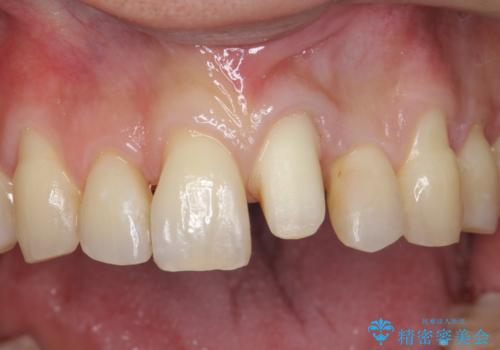

- 前歯の重なったところが虫歯になり、物理的にアプローチが難しい状態でした。

矯正治療前に虫歯を取り、歯並びが良くなってから本格的にセラミック治療を行いました。

左上1はジルコニアクラウン(スペシャル)で治しました。スペシャルの場合は写真をとり、オリジナルの色味で作成することが可能です。